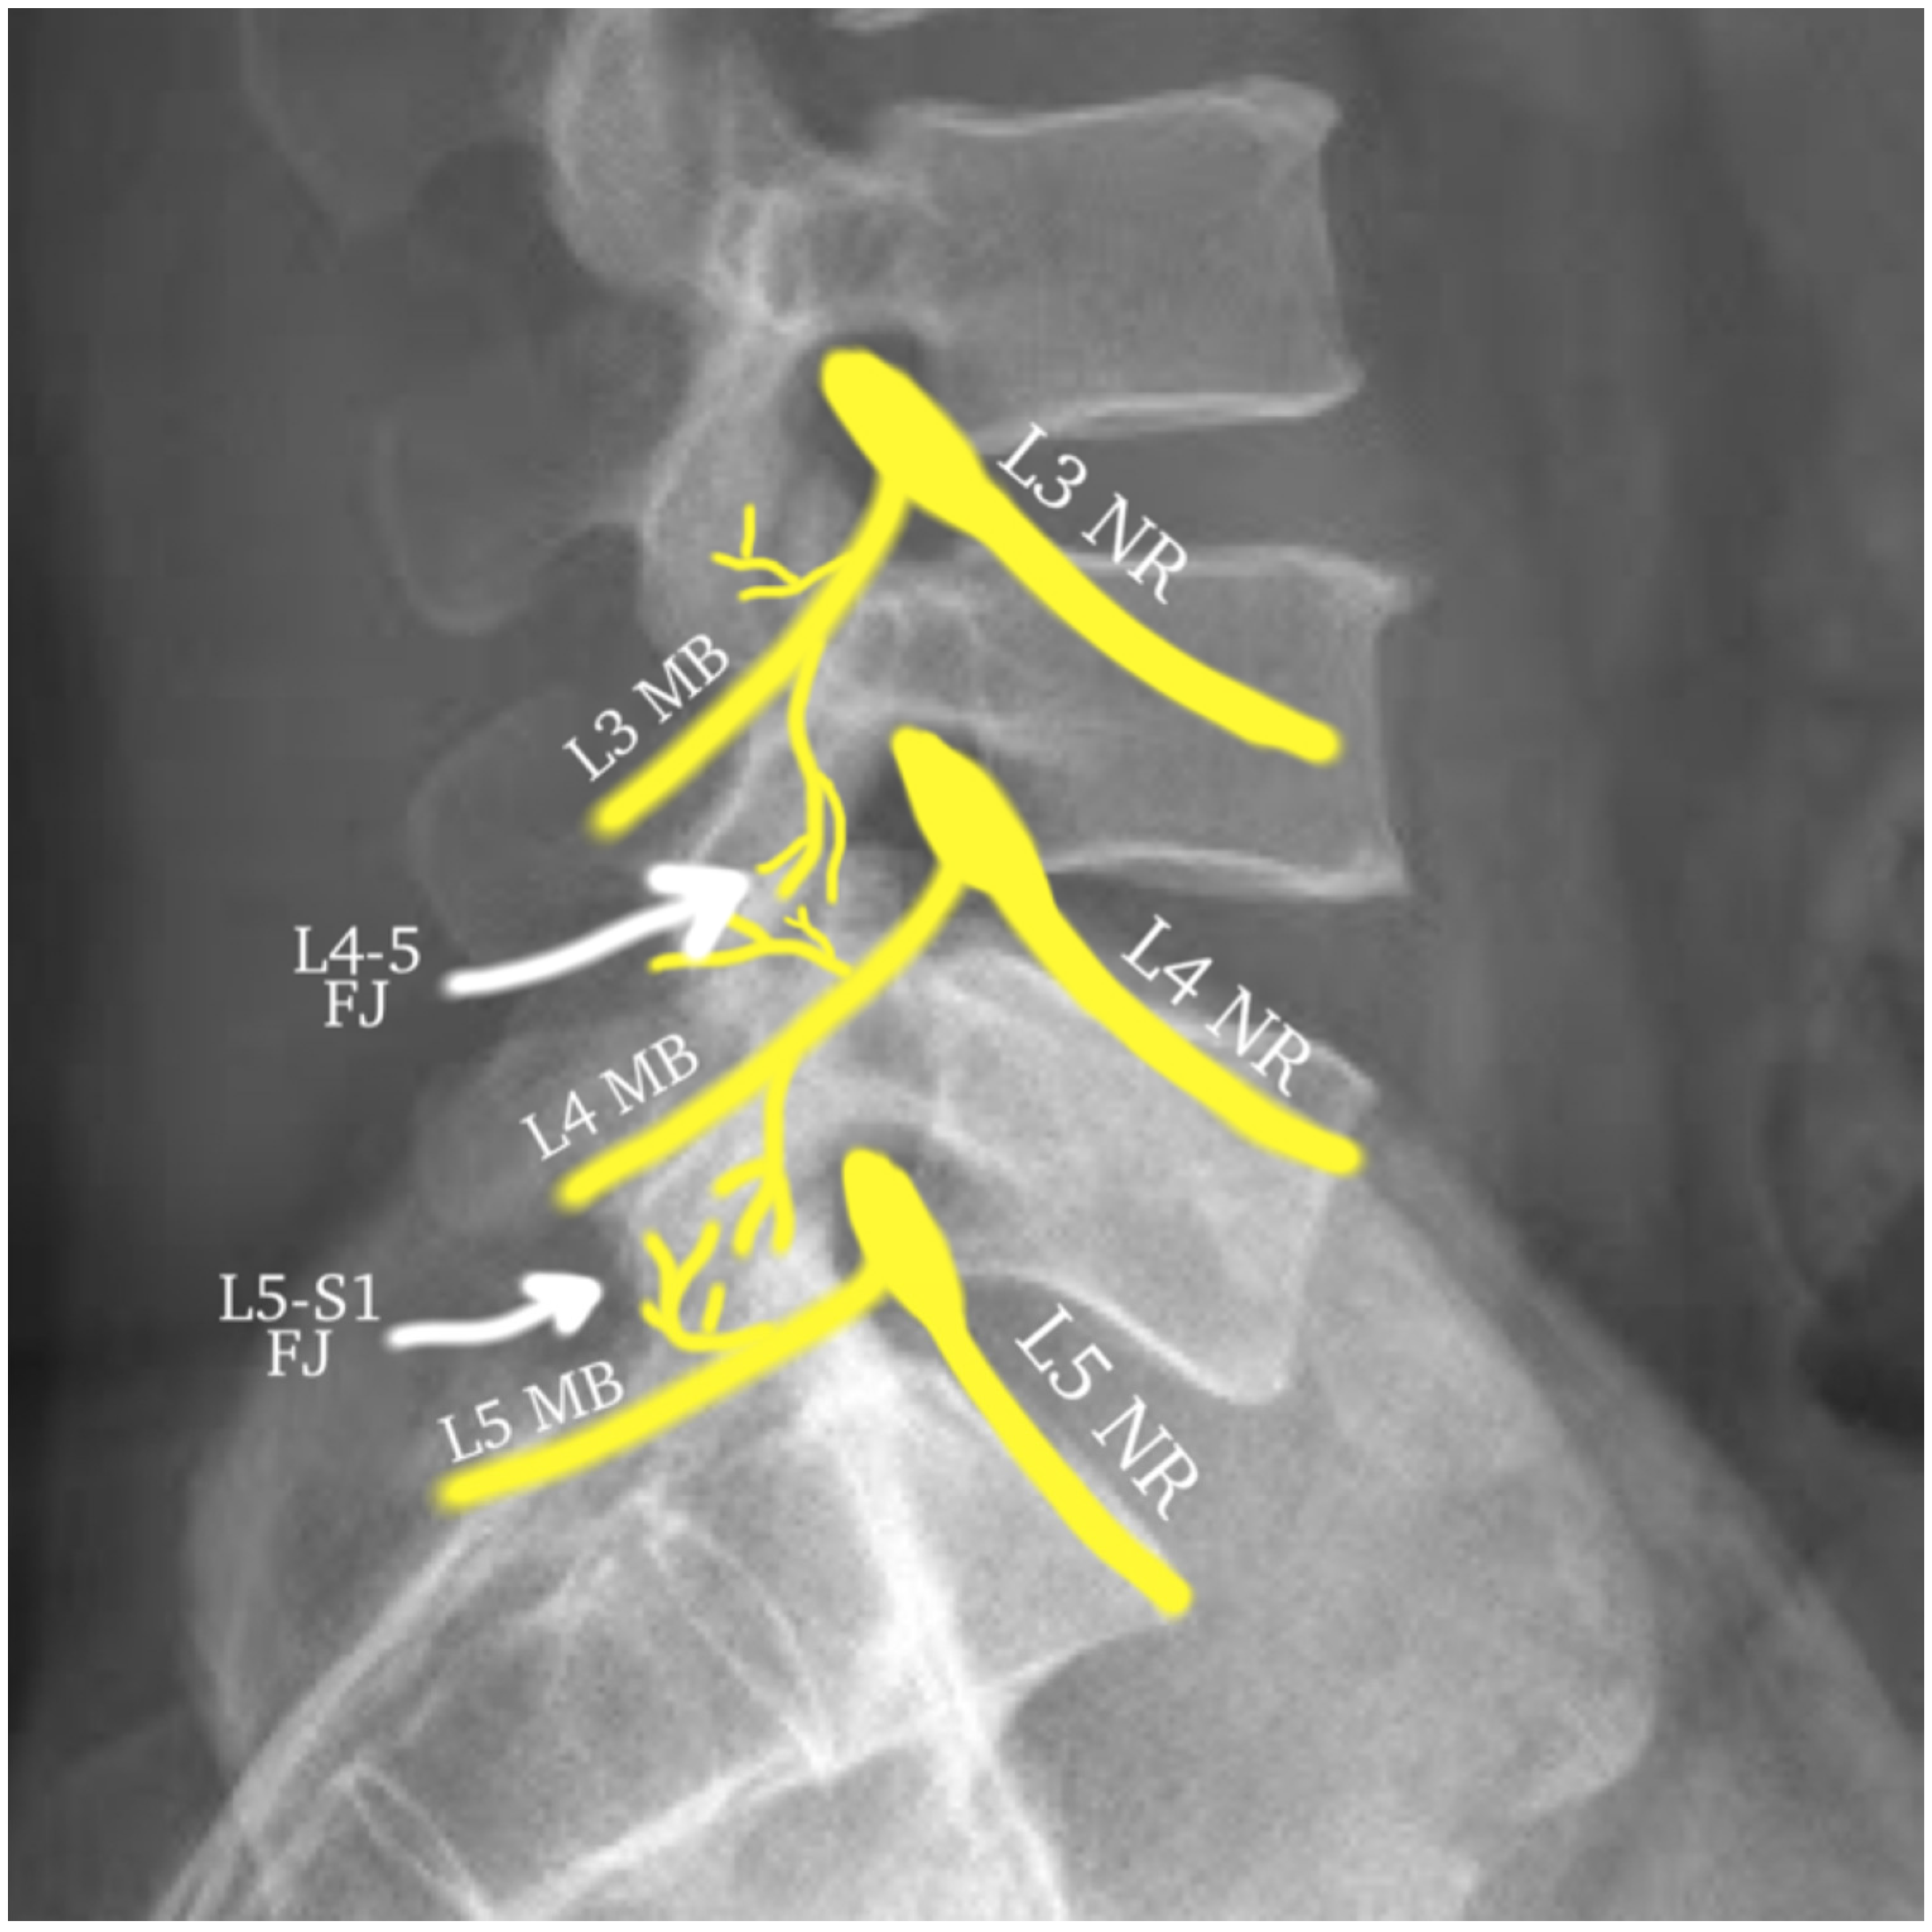

A common cause of posterior element pain stems from arthropathy of the lumbar facet (zygapophyseal) joints. The lumbar facet joints are true synovial joints with a hyaline cartilaginous surface, a fibrous capsule, and a distinct joint space that is capable of accommodating 1.0–1.5 mL of fluid. The facet joints form the posterolateral articulations, connecting the vertebral arch of one vertebra to that of the adjacent vertebra [136]. Each lumbar facet joint receives dual innervation by the medial branches of the posterior rami of the corresponding level and the level above and by the dorsal ramus proper at the L5 level (for instance, the L4–L5 facet joint is innervated by the L3 and L4 medial branches) (Figure 1) [137]. The lumbar facet joints have long been recognized as a significant cause of cLBP, as described as early as 1911 [138]. This was demonstrated further in 1963, when pain from the facet joints was reproduced when injected [139].

Figure 1.

This diagram illustrates the dual innervation of the lumbar facet joints. The L4–L5 joint is receiving innervation from the L3 and L4 medial branches, while the L5-S1 joint is receiving innervation from the L4 medial branch and L5 dorsal ramus proper (prior to dividing to the L5 medial branch). Abbreviations: NR—nerve root; MB—medial branch; FJ—facet joint.